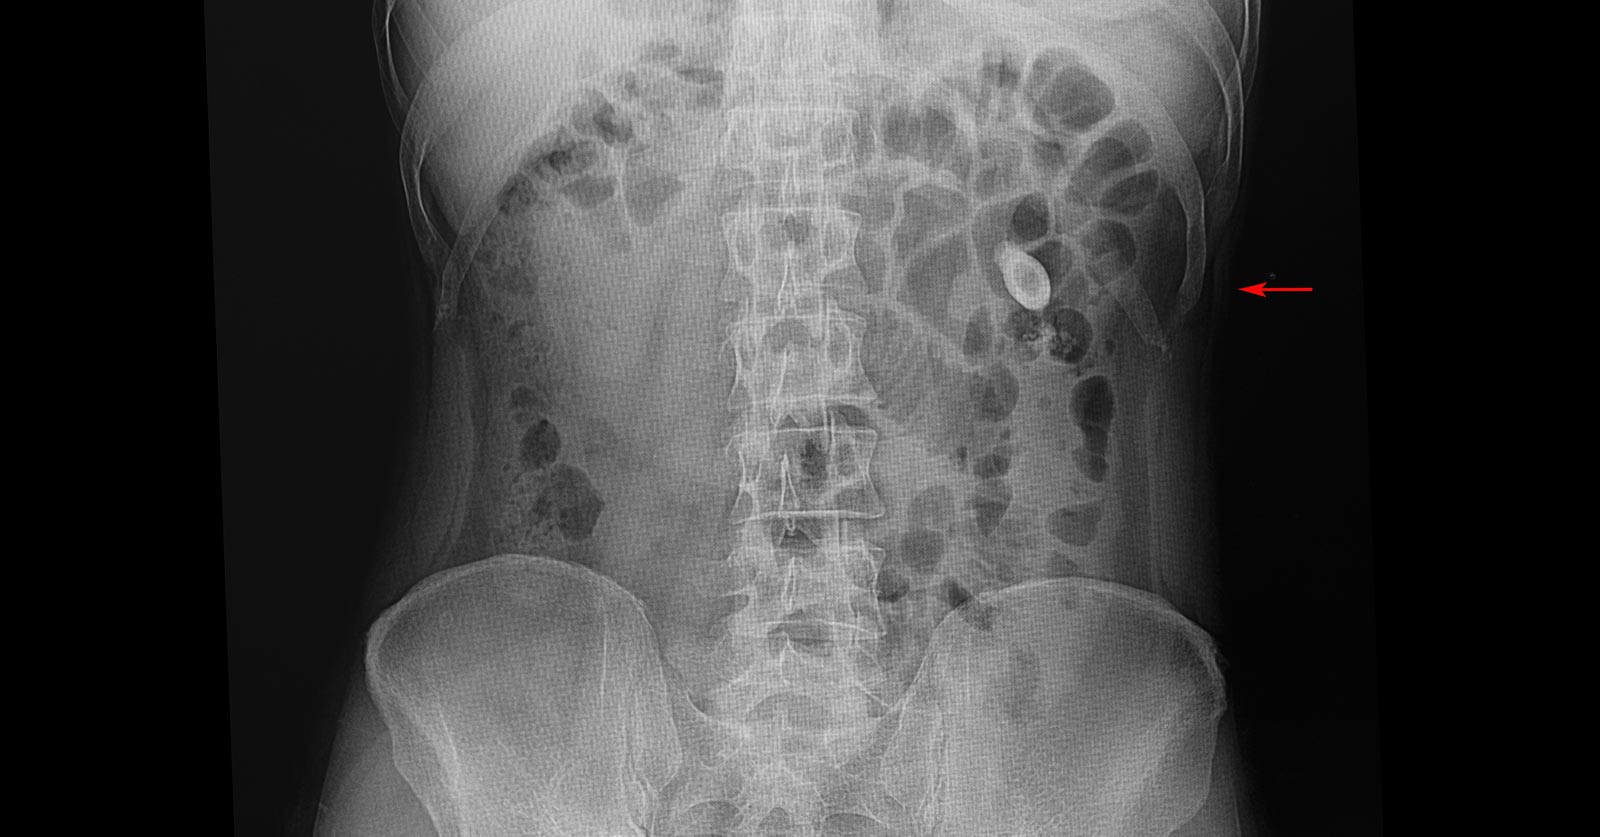

Kidney stones affect approximately 1 in 11 people in the United States, and a growing number of children, especially teenagers, are among them. A kidney stone is a small lump …

Sometimes, kidney stones can be as small as a grain of sand but some bigger stones can cause trouble in your urine flow along with a lot of pain. In …